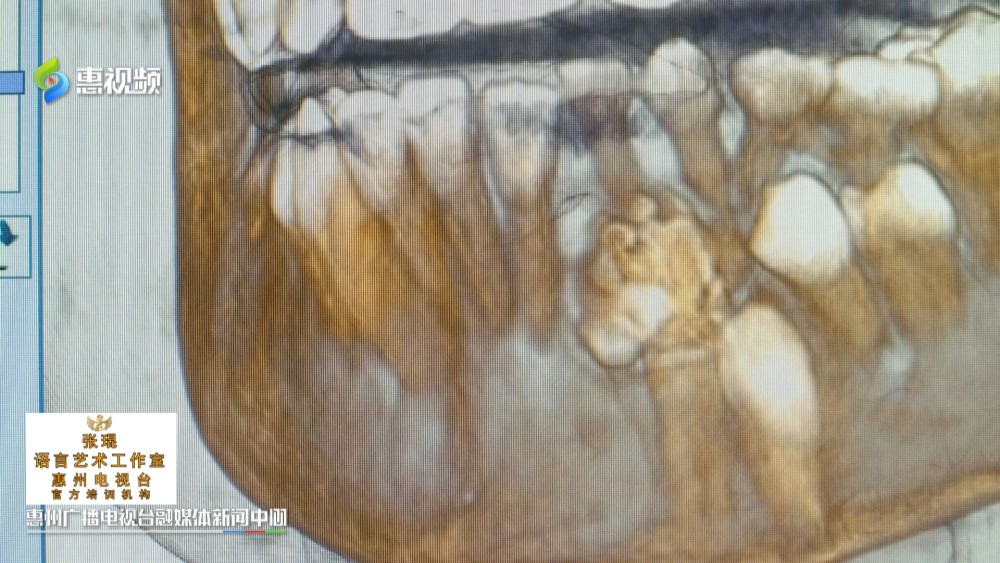

10岁的小婷,一个月前,发现左下颌骨处隆起了一个“大鼓包”,虽然不会疼痛,但肿物影响咀嚼,于是家人带她到医院就医,经诊断,医生确定是一颗“牙瘤”口腔种植,口腔正畸医生。这颗牙瘤就像石榴一样,里面密密麻麻长了25颗畸形牙齿熟悉掌握方丝工矫正技术,

惠州市第三人民医院口腔颌面外科 副主任医师 王俊文:这种算危害比较大,因为她25颗完全就压在那个恒牙的上面,导致恒牙无法长出熟练掌握口腔内科治疗,

最后,医生通过手术帮小婷摘除了肿物,取出25颗畸形牙齿中华人民共和国执业医师法。据介绍,牙瘤并非传统意义上的肿瘤,而是由成牙组织分化、发育形成的错构瘤口腔临床执业医师。与天然牙的发育形成类似,肿物中含有成熟的牙釉质、牙本质、牙骨质和牙髓组织口腔医学技术。在生长发育过程中,当牙瘤完全钙化后,这些结构错乱,或相对有序的牙体组织,会被外周的纤维结缔组织囊包裹,继而影响恒牙发育口腔修复工艺